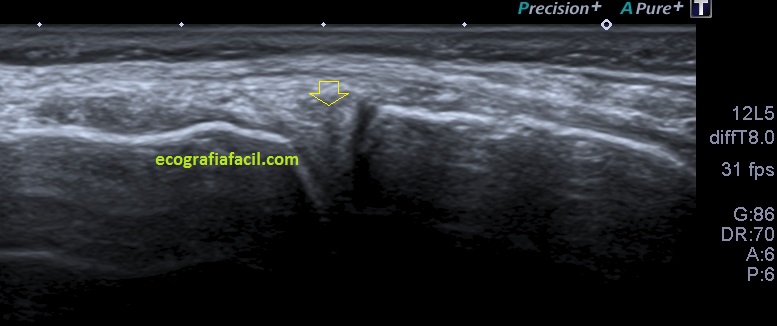

En el caso de hoy, el paciente presentaba una imagen de la zona descrita en la imagen 1 y que ves la imagen siguiente que difiere significativamente de la normalidad.

2

En esta imagen vemos la misma región que viste en la imagen 1, donde claramente ves alterada la semiología de la ecoarquitectura de menisco, heterogéneo, hundido, y en la superficie del mismo, imágenes hipecogénicas muy finas que pueden indicar afectación del mismo. Un poco más superficial e indicado con la flecha roja observas una estructura anecoica, correspondiente a líquido que luego verás en detalle en fotos posteriores.

La afectación del menisco es variable, por supuesto, verás muchos que difieran de la normalidad. En la imagen 2 has visto un menisco afectado, en la imagen 3 vas a ver otro, mira: